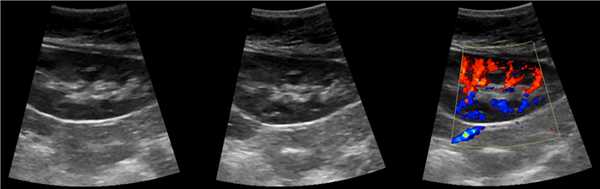

Трансплантированная почка обычно располагается вдоль поверхности подвздошнопоясничной мышцы, ее эхогенность совпадает с эхо- генностью обычной почки. Эхографические признаки отторжения трансплантата включают: патологическое увеличение размеров почки, гидронефроз, паранефральное скопление жидкости, гематомы, абсцессы и экстраренальные накопления мочи. При допплерографии почечного кровотока обычно определяется увеличение сосудистого сопротивления или полное прекращение кровотока в главной почечной артерии, междолевых артериях, дугообразных артериях (для исключения отторжения), почечной вене (для исключения перегиба почечной вены).

- УЗИ почечного трансплантата. Эхография почки является безопасным скрининговым методом, позволяющим выявить изменение размеров пересаженного органа, деструкцию паренхимы, наличие патологических изменений в паранефральном пространстве. Исследование дополняют УЗДГ почечных сосудов для комплексной оценки состояния кровотока.